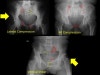

X-ray : 골반 골절(Pelvic fracture)

* 수직 불안정성을 의미하는 방사선학적 소견 : 수술적 치료 필요

제5요추 횡돌기 골절

두부방향으로 전위 > 1cm

천골 외측부 또는 좌골극 견열 골절

치골결합 이개 > 2.5cm

전위된 천골 골절

Push-pull test 상 1cm 이상의 두부 방향으로의 전위